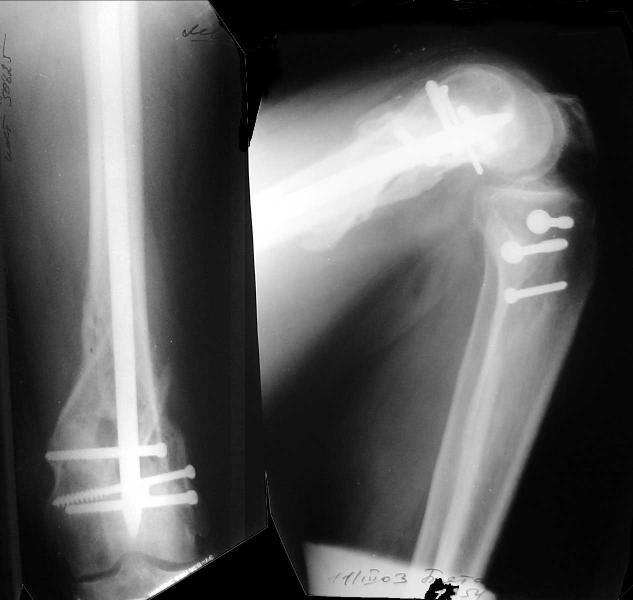

Re: Open supracondylar femur fx

And why LISS is superior here than nail?

Look what we would have done.

Zsolt Balogh 31 Октябрь 2004, 20:46

I would not say that the LISS is superior to the nail. If I would, I had not post original mail. I wanted to generate discussion. Your option is a very viable one. I feel a little bit shaky the distal femur, but it is just gut feeling no science behind it. Any way nice fixation, congarts!